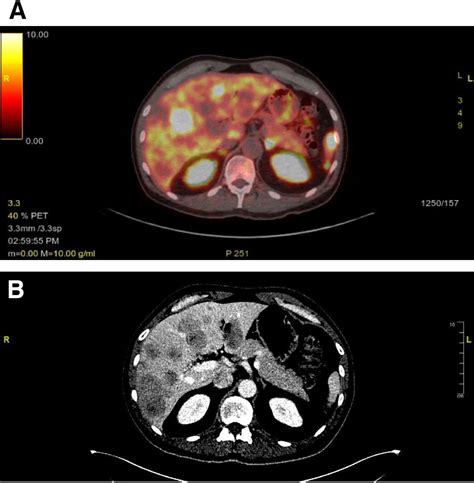

The "Dotatate" component is a radioactive pharmaceutical agent. It acts as a targeted seeking device that binds to somatostatin receptors. These receptors are often found in high concentrations on the surface of neuroendocrine tumor cells. Because these tumors "light up" when the tracer binds to them, the PET scan creates a vivid map of where these tumors are located throughout the body, even those that are too small to be detected by standard imaging.

Interpreting the Results

Once the scan is complete, the images are sent to a radiologist or nuclear medicine physician who specializes in interpreting these complex studies. They will analyze the images to identify areas of high tracer uptake, which indicate the presence of neuroendocrine tumor cells. The results are typically combined with findings from other tests and your clinical history to provide a comprehensive summary of your condition.